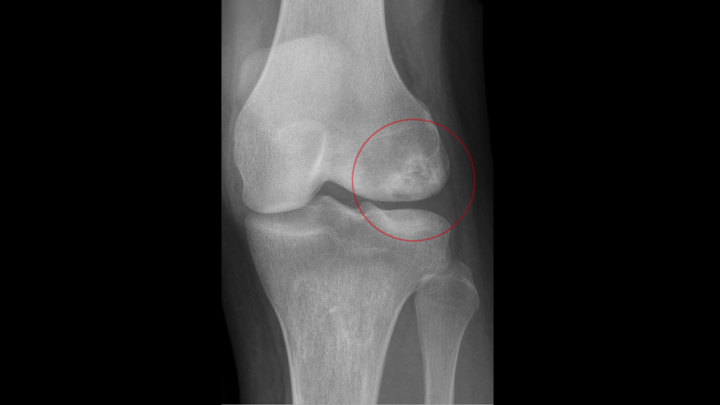

Avascular necrosis (AVN) of the knee, also known as osteonecrosis, is a condition that occurs when the blood supply to a section of bone in the knee joint is disrupted. This lack of blood flow can cause the affected bone to weaken, collapse, and eventually lead to joint damage. AVN most commonly affects the ends of bones in weight-bearing joints like the knee, and early diagnosis and treatment are important for preserving joint function and preventing further damage.

Avascular necrosis occurs when a lack of blood supply causes the death of bone tissue. In the knee, AVN typically affects the femoral condyles (the rounded ends of the thighbone) or the tibial plateau (top of the shinbone). As the bone weakens, the overlying cartilage may also become damaged, leading to pain, stiffness, and reduced knee function. AVN can progress over time, potentially causing arthritis or severe joint deterioration.